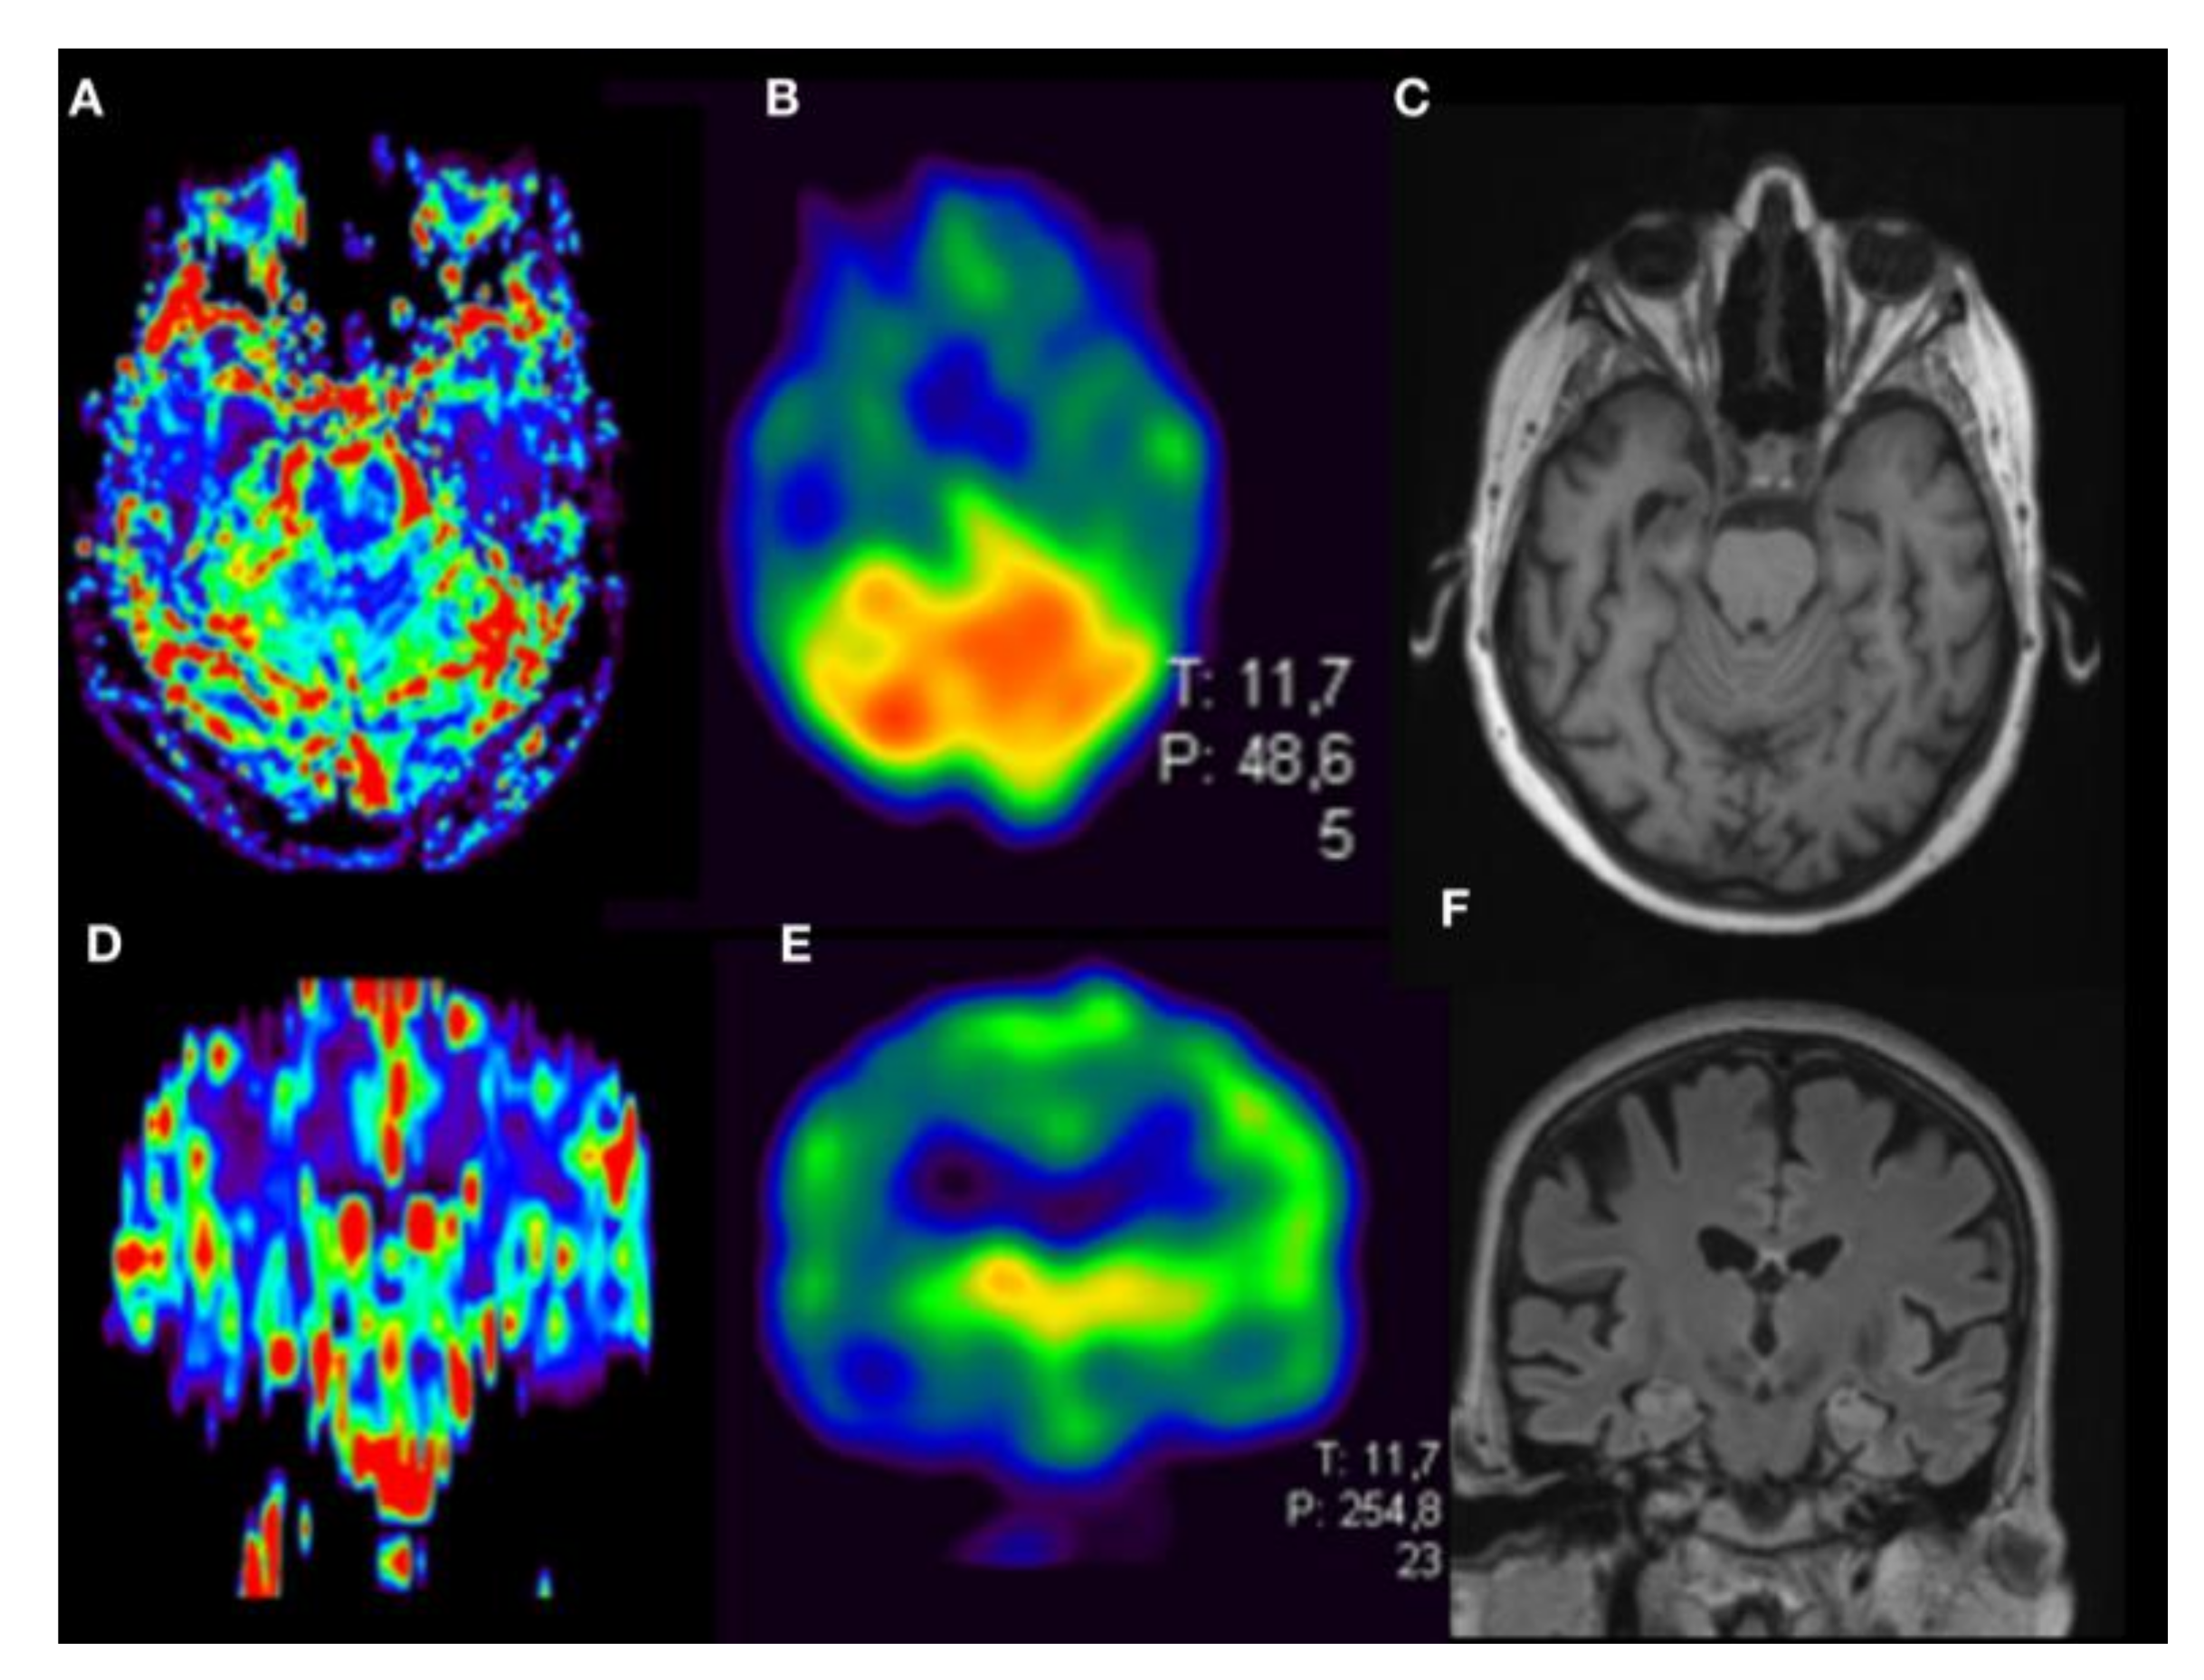

3. Results